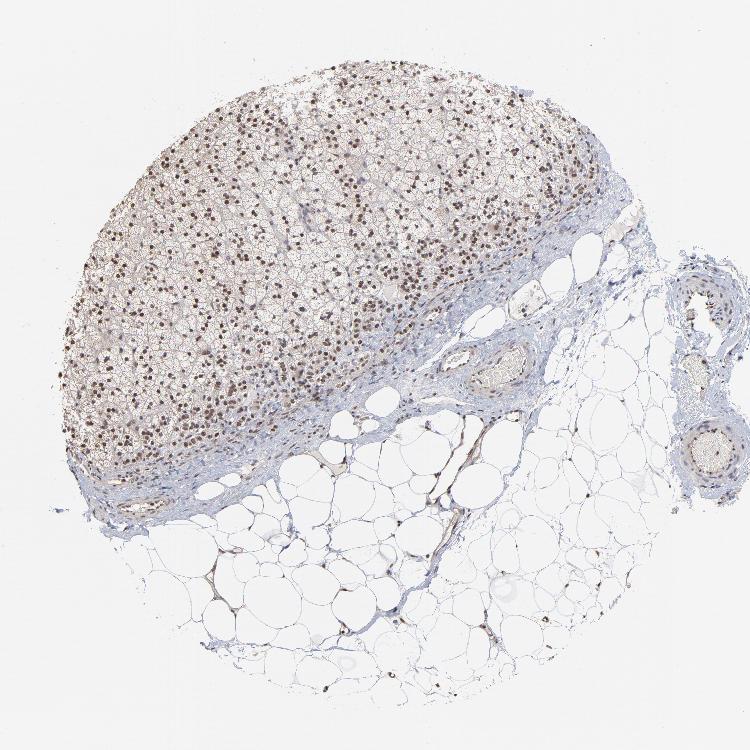

ADRENAL GLAND - Antibody stainingi

Antibody staining in the annotated cell types in the current human tissue is reported as not detected, low, medium, or high, based on conventional immunohistochemistry profiling in selected tissues. This score is based on the combination of the staining intensity and fraction of stained cells.

Each image is clickable and will lead to virtual microscopy that enables deeper exploration of all samples and also displays staining intensity scores, fraction scores and subcellular localization as well as patient and tissue information for each sample.

Antibody HPA002813

Glandular cells Medium